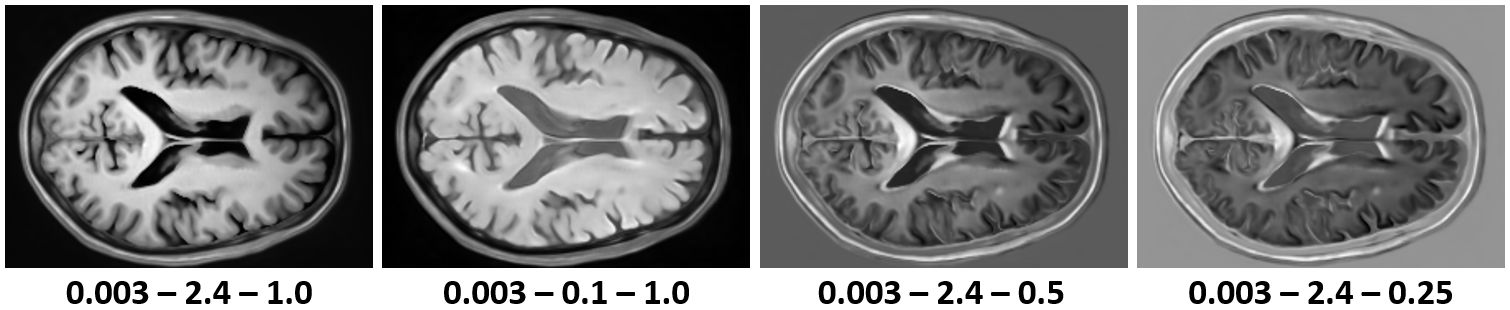

A key advantage of our physics-informed generative model over previous methods is the ability to synthesize modalities not present in the training data. Figure 3 shows how changes in the acquisition parameters affect the generated images using different signal models given a single tissue property map generated by our model. Although we can generate various novel MR contrasts, some acquisition parameter combinations can still lead to unrealistic images with bright backgrounds.

The employed signal model only considers a perfect MR scanner that does not add any noise to images. Thus, the MRI scans generated by our model do not contain any noise either Figure 5. While this might be desirable for some applications, noise is required to create realistic MRI scans. One solution could be to model the residual noise separately using another diffusion model conditioned on the noise-free MRI scan [16]. Additionally, the accuracy of the tissue property maps is limited by the number of available MR contrasts per scanning session. This issue could be addressed by introducing location-dependent priors based on the expected tissue type, such as white matter, grey matter, and cerebrospinal fluid. A more robust evaluation of the generated tissue properties would furthermore require access to real tissue property maps, which advanced quantitative MRI techniques can obtain [13].